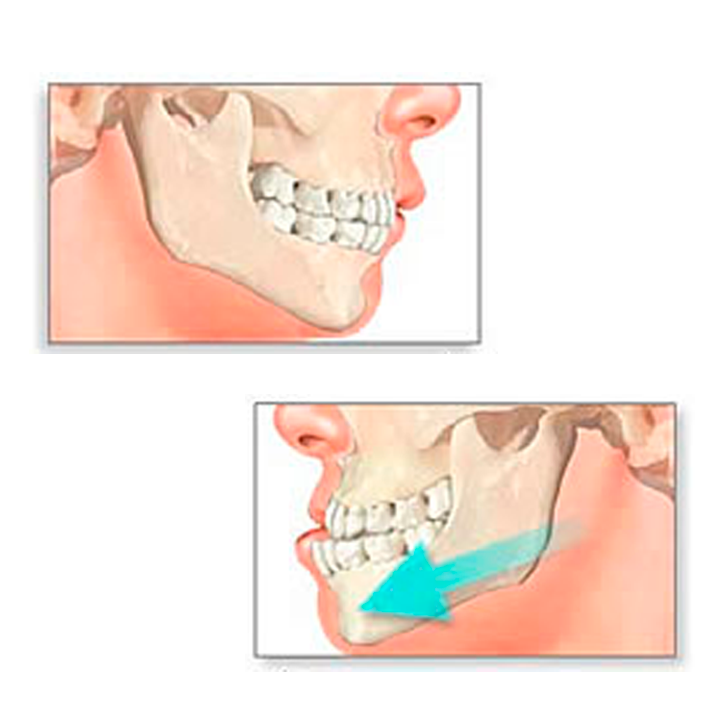

- Ver expedienteCirugía Ortognatica